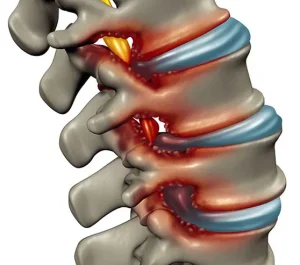

3. Disk Kaymaları (Herniated Disk)

Omurga diskleri, omurlar arasındaki yastıklar gibi işlev görür. Bu diskler yerinden kayarsa veya yırtılırsa, omuriliğe baskı yapabilir ve miyelopatiye yol açabilir. Disk kaymaları, genellikle bel veya boyun bölgesindeki omurlar arasında meydana gelir.

Omurgada meydana gelen dejenerasyon, özellikle yaşlı bireylerde miyelopatiyi tetikleyebilir. Omurlar arasındaki disklerin zamanla yıpranması ve omurga kanalının daralması (spinal stenoz), omuriliğe baskı yaparak miyelopatiye yol açabilir. Bu durum genellikle servikal miyelopati ile ilişkilidir.